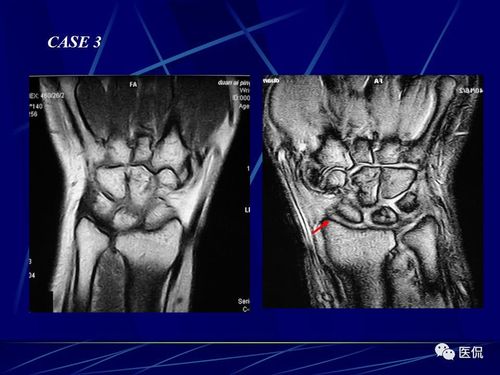

腕关节的mri解剖影像及诊断#医学影像经典ppt